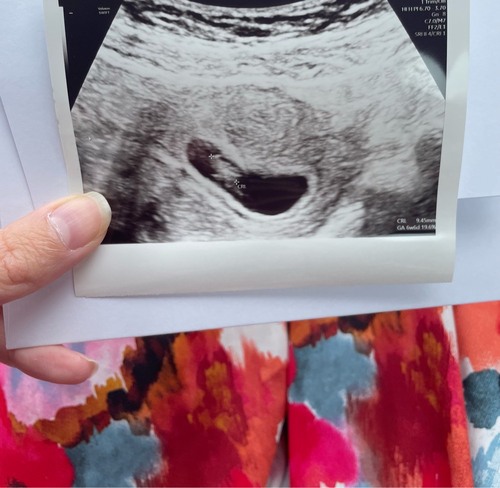

M鈥檔 eerste echo, straks terug bellen voor nieuwe echo eind augustus omdat ik nog maar 5 weken was we dachten langer 馃馃徎馃馃徎